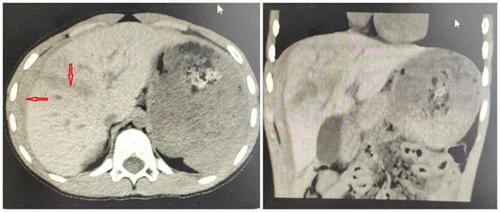

五,肝破裂出血

ct诊断:高度怀疑肝左内叶肝破裂. 手术

腹部外伤肝破裂

查体可见小朋友右侧肋弓处皮肤擦伤,ct片示右肝叶破裂,裂口长达8